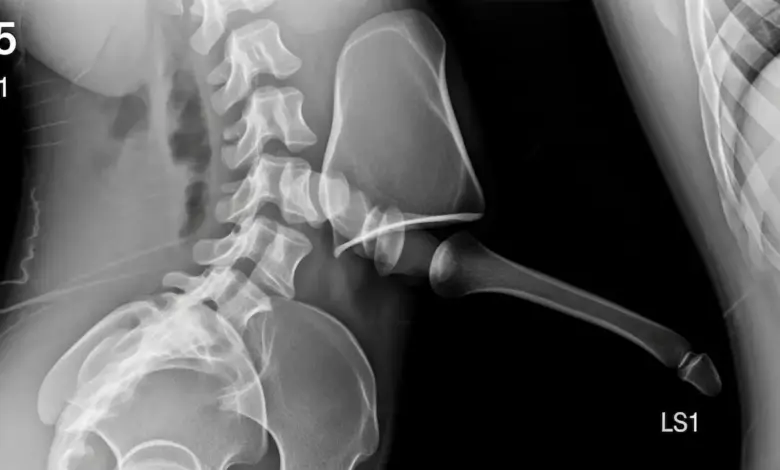

Exames que confirmam

O caminho começa com história clínica e exame físico detalhados. Em seguida, os exames de imagem definem o grau e estabilidade.

- Radiografias AP e perfil, com medidas de Meyerding e dos ângulos.

- Radiografias dinâmicas em flexão e extensão, para avaliar a instabilidade.

- Ressonância magnética, para observar o disco, facetas, canal e raízes.

- Tomografia, útil em dúvidas anatômicas e planejamento cirúrgico.